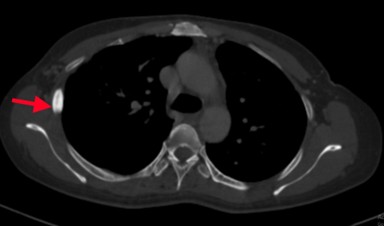

Bệnh nhân đi khám tại bệnh viện Bạch Mai được chụp cắt lớp vi tính lồng ngực phát hiện các đám tổn thương đông đặc phổi 2 bên, tổn thương đặc xương không đều các đốt sống D5, D8, D11 và xương sườn IV bên phải.

Hình 1: Hình ảnh tổn thương phổi trước điều trị: các đám tổn thương đông đặc, ranh giới không rõ, lan tỏa nhu mô phổi 2 bên.